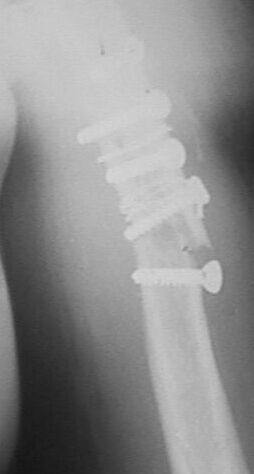

Больная оперирована в апреле 2002 г, иммобилизация в течение 3 месяцев.После операции были явления неврита лучевого нерва, которые в последующем исчезли. Во время проведения ЛФК отмечает появление болей. В настоящий момент имеется патологическая подвижность в месте перелома, деформация плеча. У нас мнения разделились в тактике дальнейшего ведения.

1. провести репозицию закрытую и продолжить иммобилизацию гипсовой повязкой.мотивируя опасностью повторного повреждения лучевого нерва при повторной операции.2. провести открытую репозицию, удаление фиксаторов, остеосинтез накостный костной пластикой.3. репозиция, фиксация отломков аппаратом внешней фиксации спицестержневого типа.

Перелом 7 мес. назад, формируется псевдоартроз. По мне, слишком много "железа" в месте перелома. Особенно мешают проволочные петли, метод древний

и не рекомендуемый на Западе для трубчатых костей. Витальность и регенеративность кости по всем перечисленным причинам выглядит плохо.

На мой взгляд необходимо извлечь "железо" и это можно сделать нетравматично.

Сегодня предпочитают слепой внутриканальный гвоздь сверху вниз. Опция - Илизаров. Накостная пластина + костный графт проблематичны в смысле

повреждения нервов, инфекции и необходимости длинной пластины.

Считаю, что винты Вам придётся удалять.

В противном случае будет весьма затруднительно восстановить правильную ось конечности и добиться сращения. Соответсвенно, если уж залезите, то лучше синтезировать узкой LC DCP.